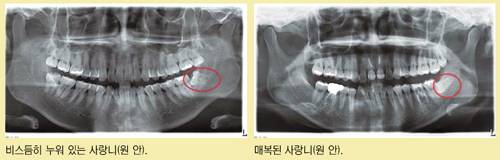

사랑니는 대부분 비정상적인 모양으로 나와, 중요한 기능을 하는 어금니에 충치나 잇몸 질환을 유발시키는 원인이 된다. 지오치과 수원점 명우천 대표원장은 "얼굴형의 변화로 턱이 좁아지며 사랑니가 좁은 공간으로 나오다 보니 다른 치아와 달리 비스듬히 나오거나 잇몸 뼈 안쪽에서 나오지 못하는 일도 발생한다"고 설명했다.

'매복 사랑니'라고 불리는 숨어 있는 사랑니, 밖으로 나왔더라도 비뚤게 나온 사랑니는 가급적 뽑아야 한다는 게 많은 치과 전문의들의 견해다.

매복 사랑니는 바로 옆 어금니 뿌리를 압박해 염증을 일으키고, 심하면 턱뼈 안에 낭종이나 종양을 발생시키기 때문이다. 이 같은 낭종은 인접 치아나 신경·턱뼈에 영구적인 손상을 일으킬 수도 있다. 비뚤게 나온 사랑니 역시 충치나 잇몸 염증을 유발하기 쉽고, 어금니까지 사랑니에서 옮아온 충치로 손상되는 일이 많다. 또 좁은 자리를 뚫고 나오면서 옆으로 다른 치아를 밀어내 치열을 불규칙하게 만드는 원인이 되기도 한다.